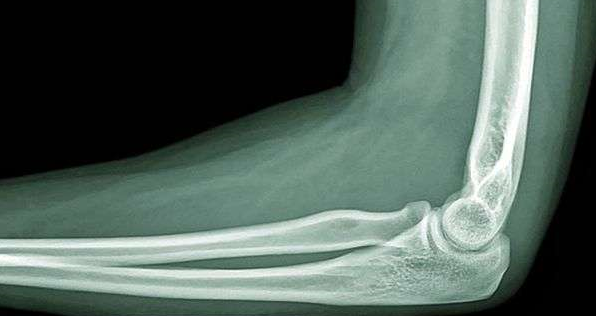

ПЕРЕЛОМ ЯКОЇ КІСТКИ І ЯКОЇ ЇЇ ЧАСТИНИ ВИ БАЧИТЕ НА РИСУНКУ?

варіанти відповідей

ДИСТАЛЬНОГО ДІАФІЗА

HUMERUS

ULNA

RADIUS

ПРОКСИМАЛЬНОГО ЕПІФІЗА

ДИСТАЛЬНОГО ЕПІФІЗА

ДІАФІЗА

МЕТАФІЗА